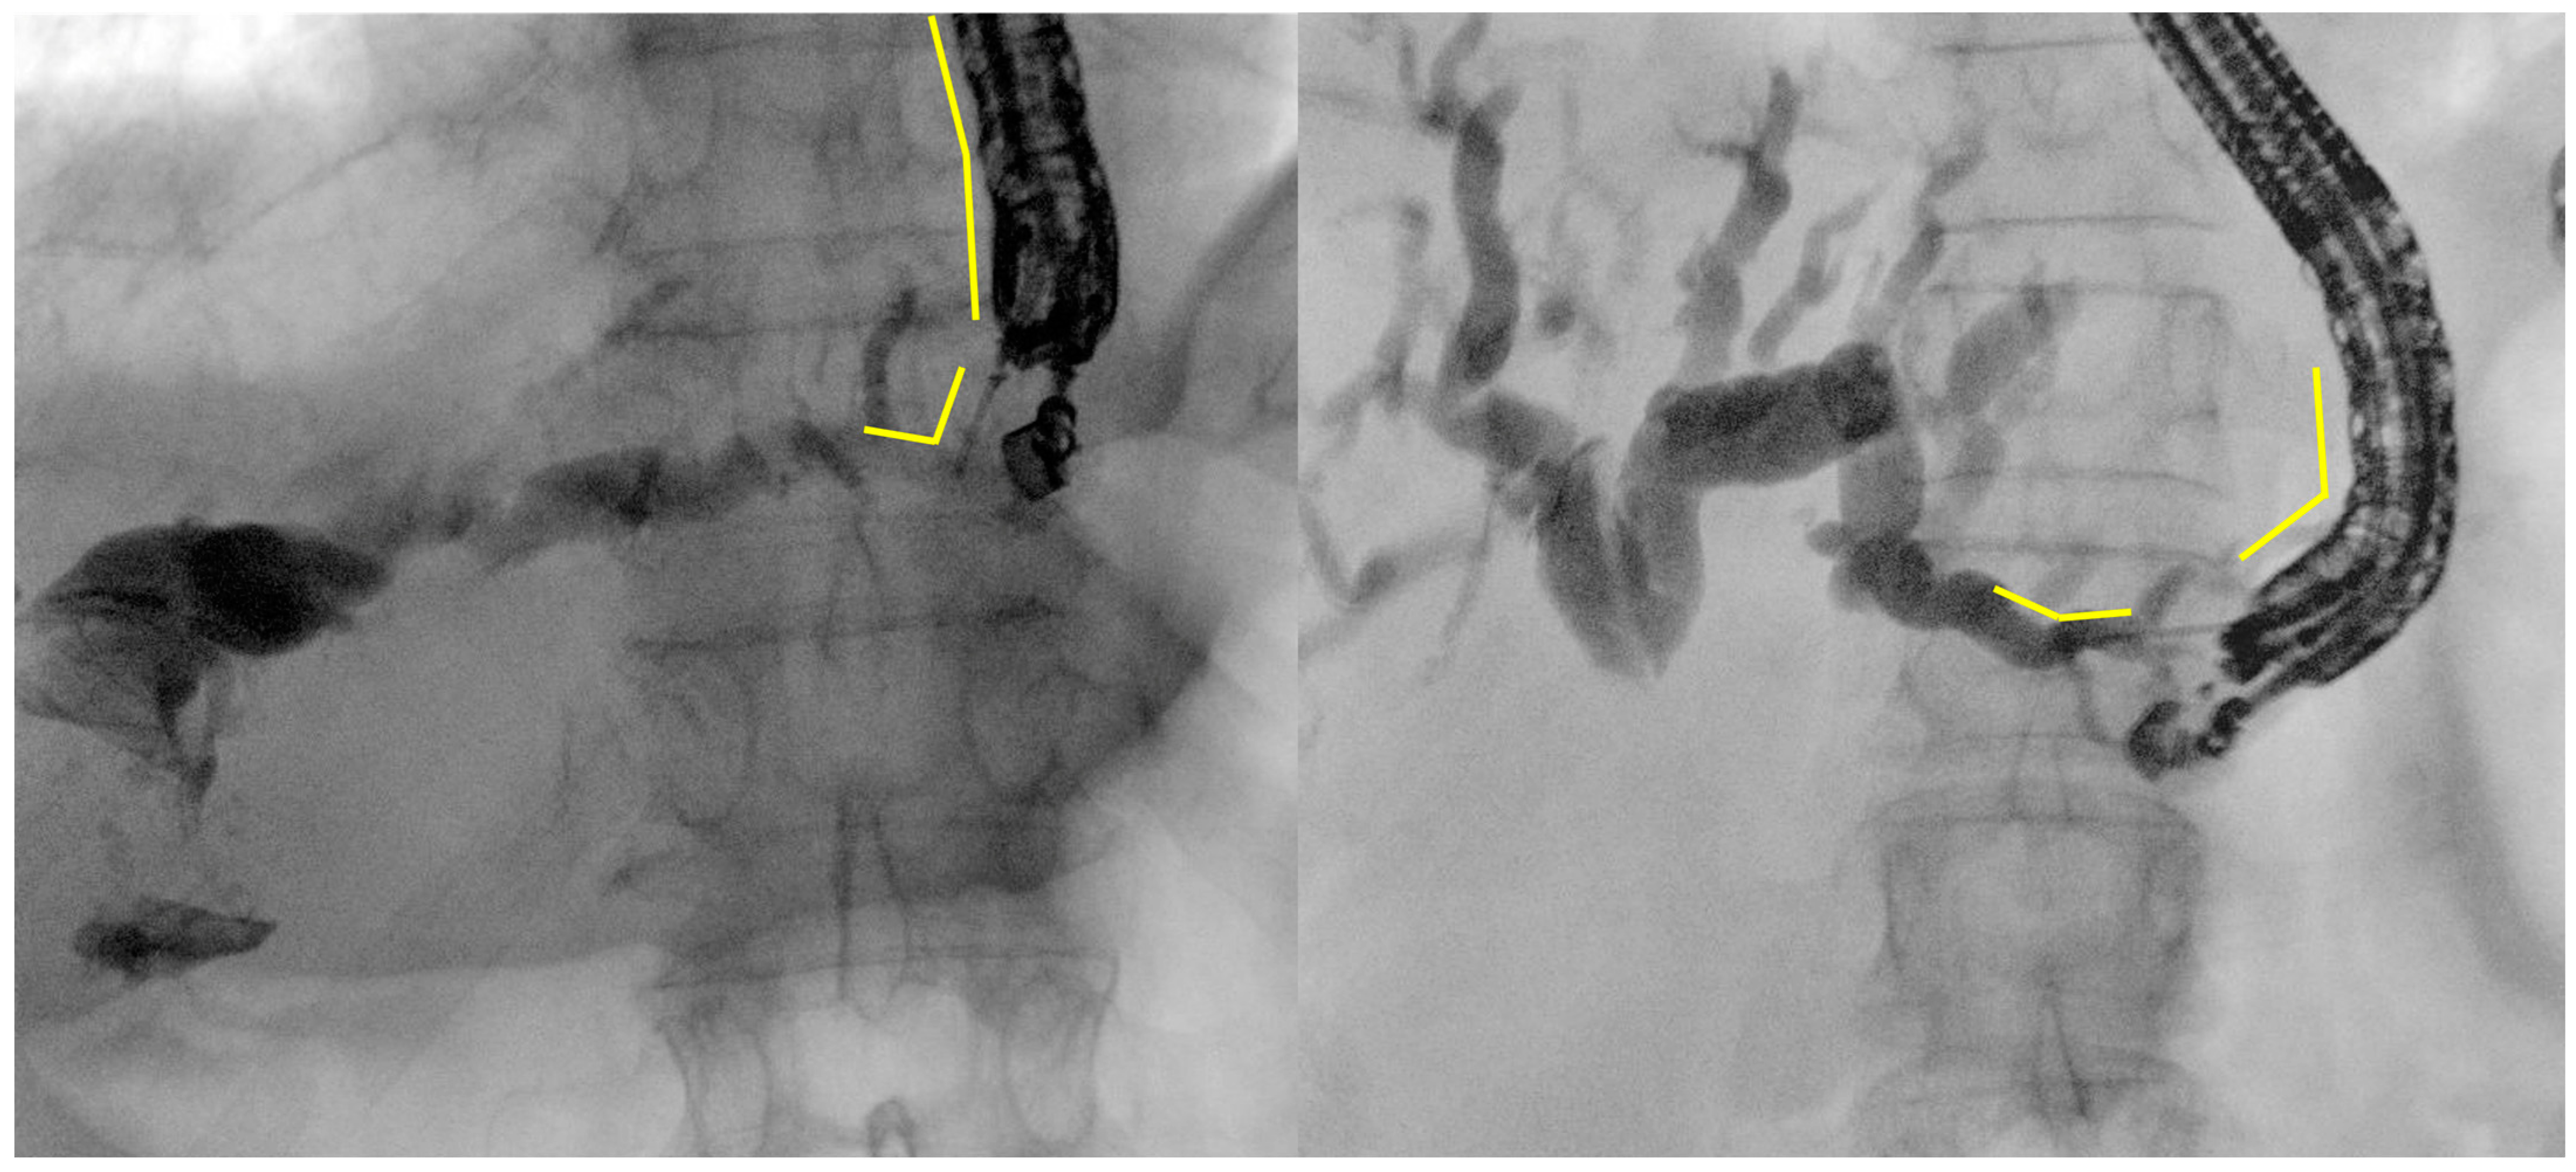

- Intrahepatic bile duct puncture

- Fluoroscopy and guidewire manipulation into the biliary tree